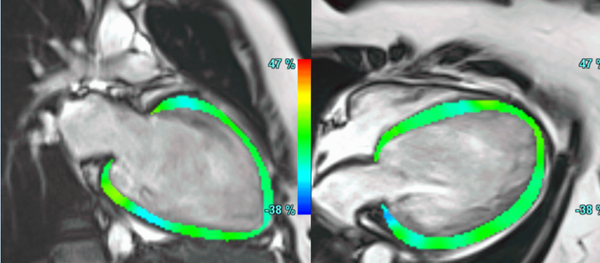

A common clinical presentation of LBBB induced cardiomyopathy is described in this post. It is always dilemma that if LBBB is cause or effect of dilated cardiomyopathy. However CMR can help in differentiating it from other causes and also in predicting response to device therapy. Utilise CMR to the fullest.